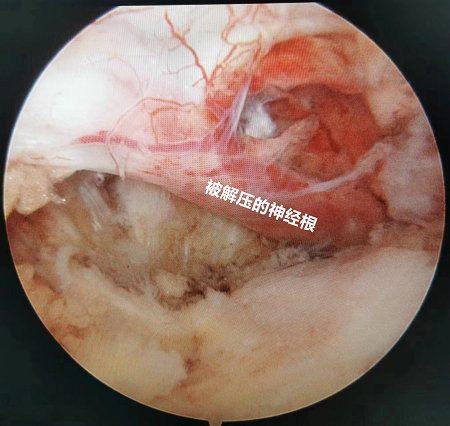

术中镜下观及术后切口照片

与脊柱开放手术一样,镜下视野清晰,减压更加彻底,疗效更加确切。而不同的是,手术切口小、创伤更小,术后康复更快。